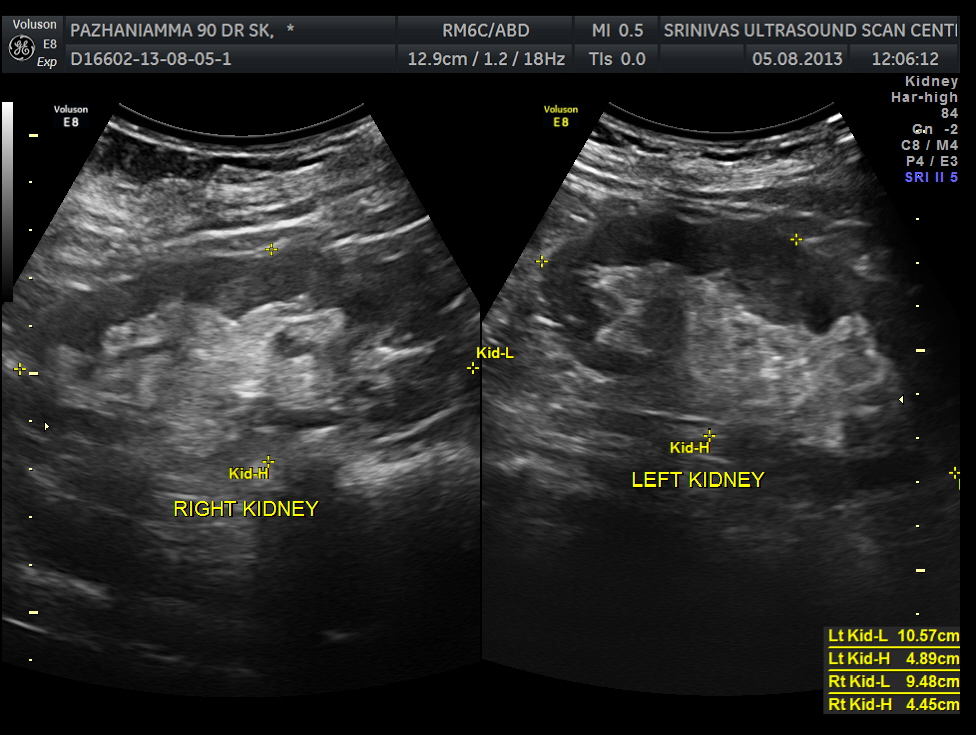

pancreas, spleen and both kidneys were normal.